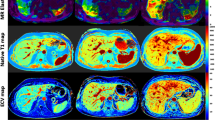

Compared to patients with AIH and no significant fibrosis (< F2), patients with significant fibrosis (≥ F2) had markedly increased hepatic native T1 relaxations times (548.8 ± 40.7 ms vs. 620.3 ± 66.3 ms; P = 0.003) and hepatic ECV values (27.1 ± 3.2% vs. 38.7 ± 18.9%; P = 0.039). There were no significant differences in hepatic T2 relaxation times between both groups (50.7 ± 4.2 ms vs. 50.5 ± 6.5 ms; P = 0.920). Also, no significant difference in fat fraction was present in both groups (5.3 ± 4.6% vs. 3.2 ± 1.5%, P = 0.135). MRE-based liver stiffness and hepatic parametric MRI results are given in Table 2. Furthermore, we found a strong correlation between MRE-based liver stiffness and hepatic native T1 (r = 0.69, P < 0.001) as well as hepatic ECV (r = 0.80, P < 0.001, see also Fig. 1). There were also significant correlations between clinical fibrosis scores such as FIB-4 and APRI and hepatic native T1 (for both scores, r = 0.49, P < 0.05). Also, hepatic ECV showed a significant correlation with FIB-4 score (r = 0.39, P = 0.04). We found no correlations between hepatic T2 and MRE-based liver stiffness as well as clinical fibrosis scores (FIB-4 and AST/ALT Ratio). A correlation matrix is given in Table 3. Representative images from patients with and without significant fibrosis are given in Fig. 2.